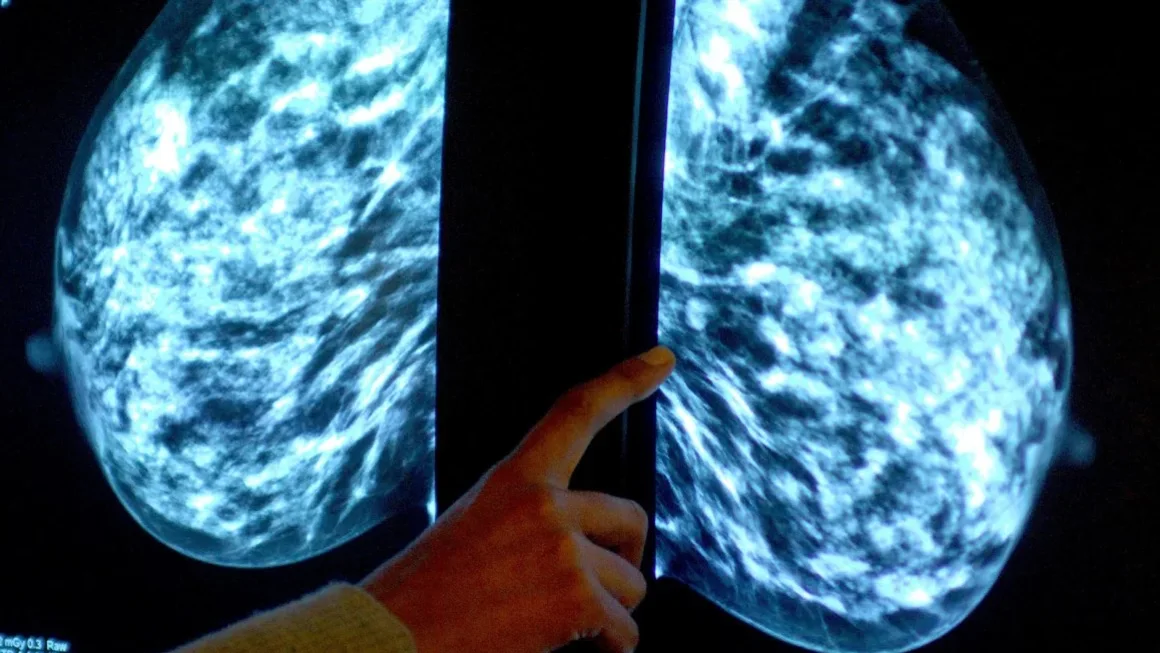

El informe está contenido en el boletín epidemiológico de la Semana 03 del Ministerio de Salud Pública, que destaca que entre los mayores casos está el cáncer de mama con 2,070, en ese período, cáncer de próstata,  que ocupa el segundo lugar con 1,249 casos, cáncer de cérvix, que registra 728 casos, cáncer colorrectal con 573 casos detectados y Leucemia con 440 casos que afectan a ambos sexos.